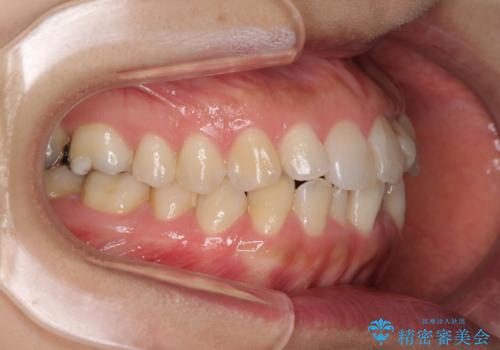

- 前歯の捻れを気にして来院された患者様です。

上顎前歯が捻れて前方に飛び出しており、下顎前歯もそれに沿うようにデコボコとなっていました。

IPR(歯と歯の間を削る処置)によりスペースを獲得して上下前歯のデコボコを改善し、インビザラインにて矯正治療を行うこととしました。

捻れていた前歯の形態が、先端が欠けていたり、一部むし歯処置により左右非対称の形態となっていたため、なかなかゴールが定まらず、治療期間がかかってしまいました。